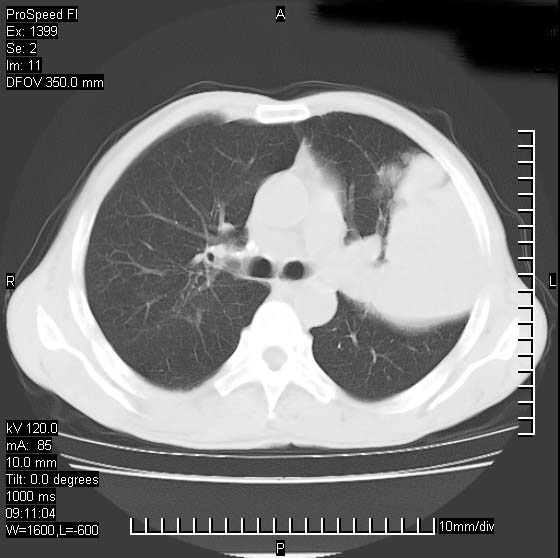

以下是引用rgsyyf在2007-1-19 11:05:00的发言:[br]左肺上叶见形态不规则巨大软组织肿块影,边缘呈分叶征,纵隔内隆突下见肿大淋巴结,右肺内另见一不规则结节影 .考虑:左肺周围性肺癌伴纵隔即右肺内转移.